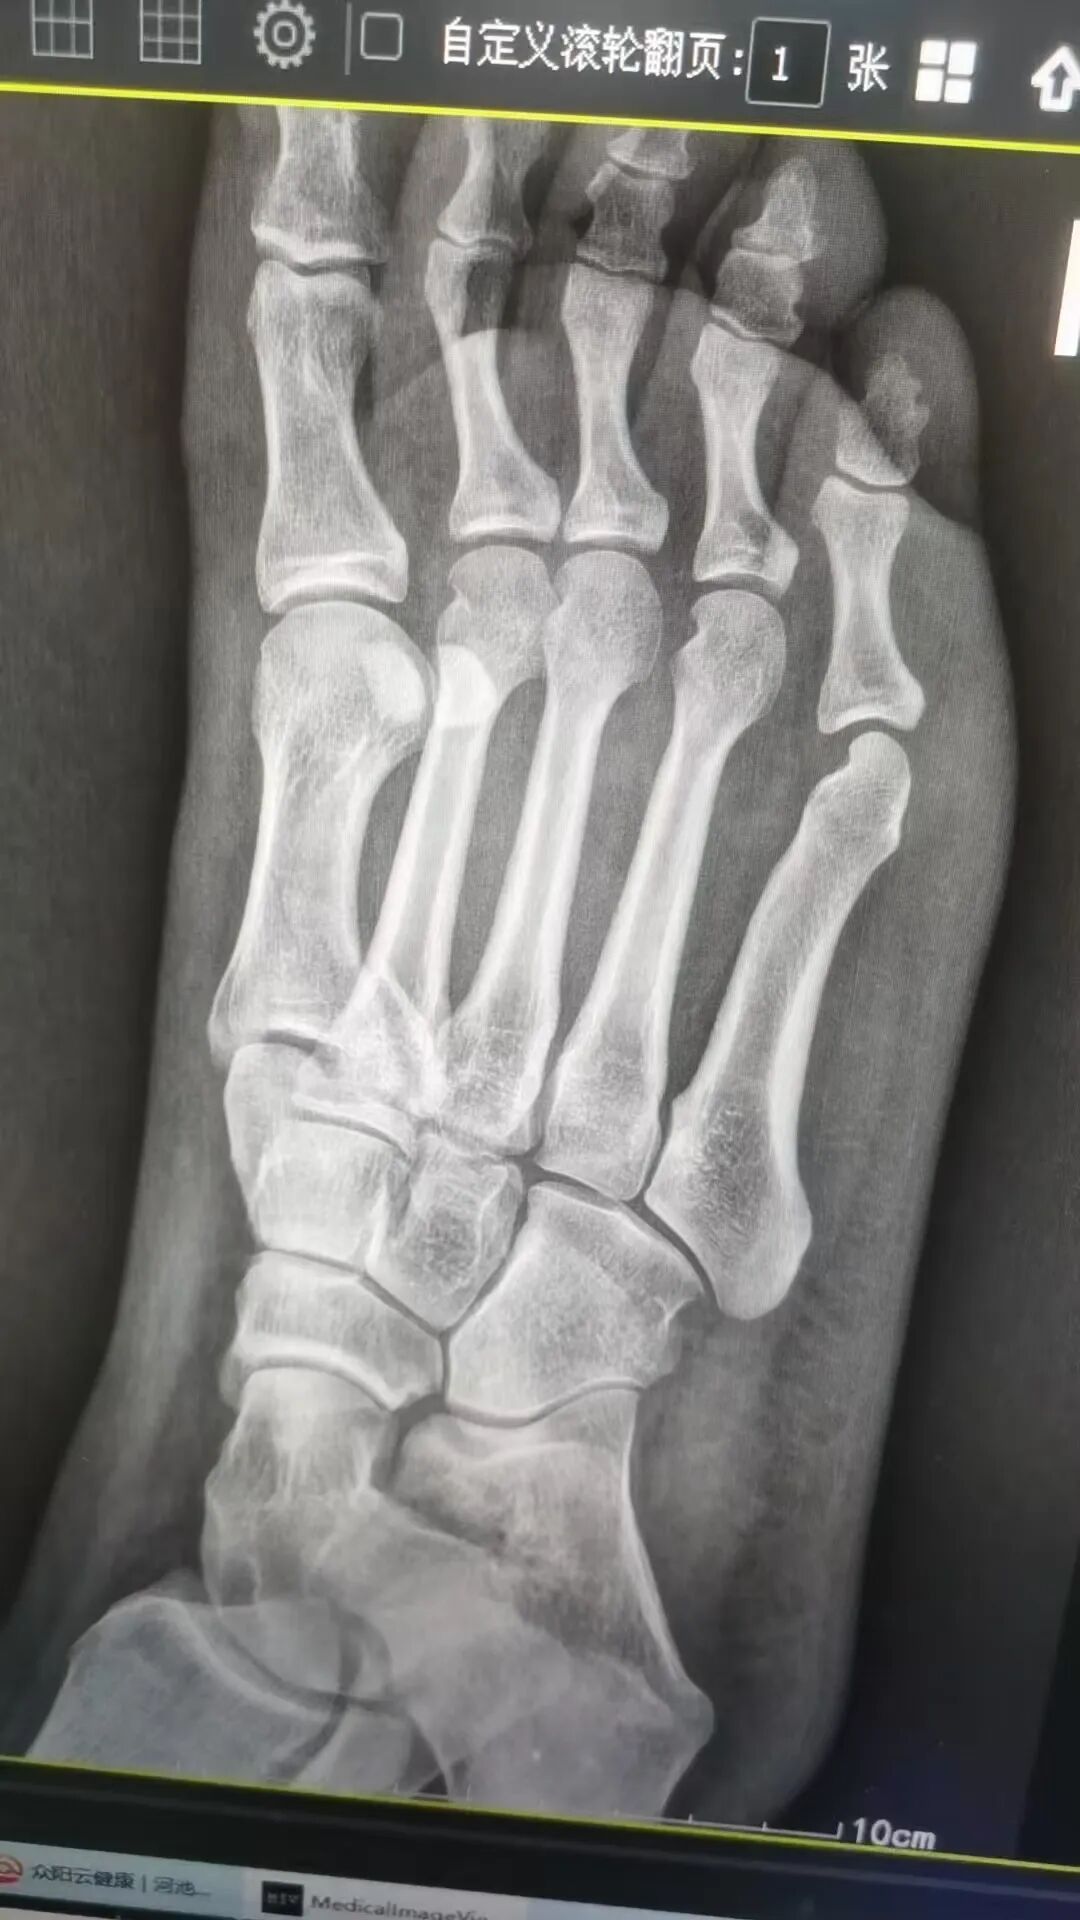

据悉,今年春节假期期间,家住南丹县的唐女士在行走时不慎跌倒,伤及右足部,伤后即感右足部呈持续性胀痛,右脚不能站立及行走,在家休息一天后,患处肿痛未缓解,遂至市中医医院骨伤科一病区就诊。经医生查体并行DR等辅助检查后,唐女士被诊断为“右足第一跖骨骨折”收治入院。

△术前